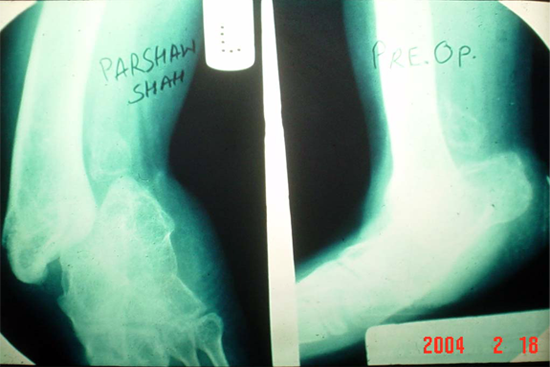

Limb Lengthening